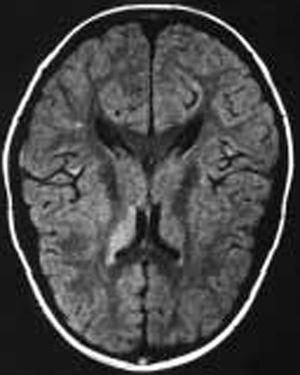

La evolución del paciente ha sido favorable sin tratamiento. Actualmente el paciente se encuentra asintomático con fondo de ojo normal y campimetría visual prácticamente normal (ojo izquierdo 108/120, y ojo derecho 112/120) (fig. 2).

Figura 2.Caso 2. Lesiones sugerentes de microinfartos.

En el fondo de ojo se apreció una lesión tipo pars planitis bilateral. La TC fue normal. La punción lumbar objetivó una PIC de 420 mmH2O. La citología, bioquímica y cultivos fueron normales. La RM craneal destacaba hiperseñales en secuencias T2 inespecíficas en la sustancia blanca frontal adyacente al asta frontal del ventrículo lateral izquierdo (fig. 1). La resonancia craneal por angiografía fue normal. La agudeza visual de 0,8 en ojo derecho y 0,7 en ojo izquierdo. El estudio de autoinmunidad fue normal. En el estudio de hipercoagulabilidad presenta mutación del gen del FVL en estado de heterocigosis, con una resistencia a la proteína C activada (ratio) de 1,67. El resto del estudio de coagulación y homocisteína fue normal.